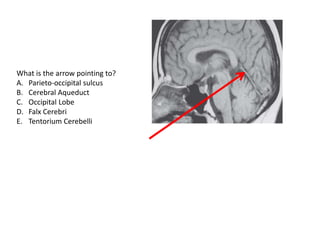

What is the arrow pointing to?

A. Parieto-occipital sulcus

B. Cerebral Aqueduct

C. Occipital Lobe

D. Falx Cerebri

E. Tentorium Cerebelli